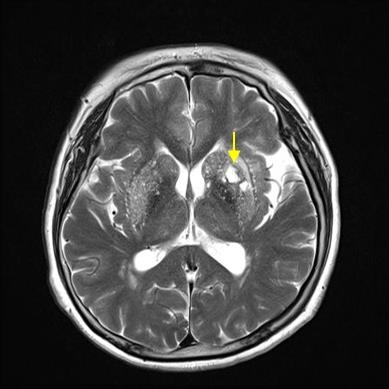

허혈성 뇌졸중은 발생 기전에 따라 대혈관 질환에 의한 뇌경색, 심인성 뇌경색 또는 심인성 뇌경색, 소혈관 질환 또는 틈새 뇌경색, 기타 드문 이유가 되는 것에 의한 뇌경색으로 나누어져요. 에피소드는 일정 기간 동안 증상이 완전히 가라앉는 경우입니다.

허혈성 뇌졸중의 대표적인 이유가 되는 것은 고혈압, 당뇨병, 고지혈증 등으로 인해서 뇌에 혈액을 전달하는 혈관에 동맥경화(동맥경화)가 발생하여 뇌로 가는 혈류를 차단하는 것입니다.